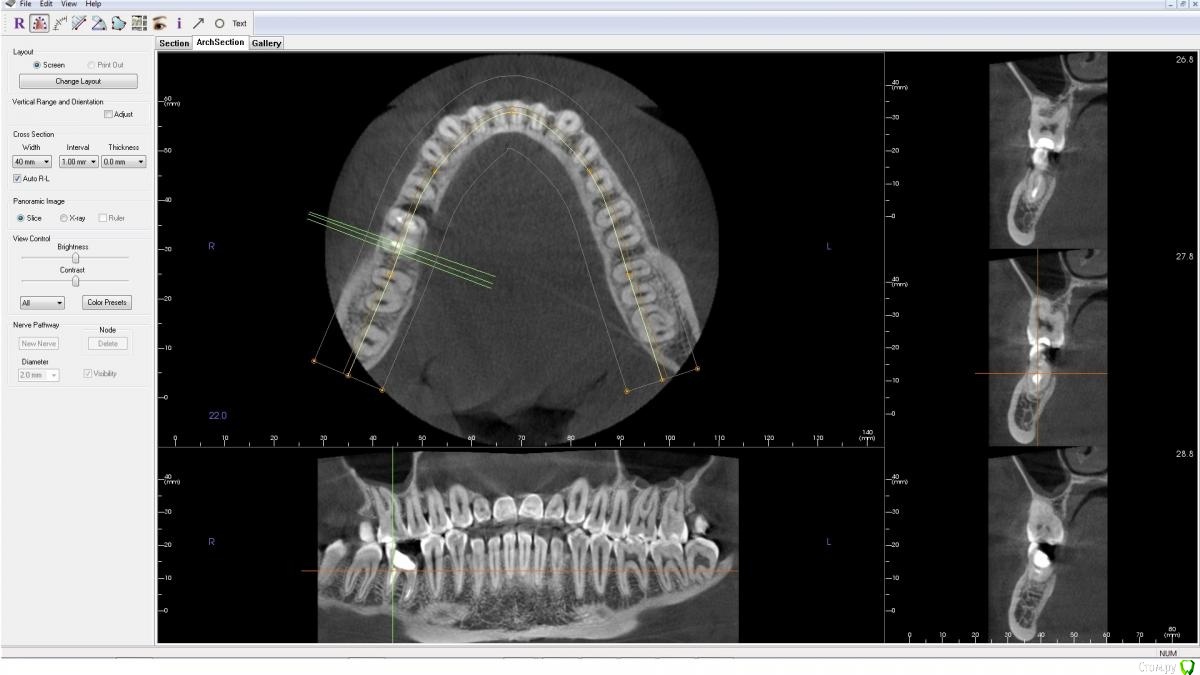

AlenaDM Опубликовано 17 февраля, 2021 Поделиться Опубликовано 17 февраля, 2021 (изменено) Добрый день.Сильно разрушен зуб. Ищу варианты протезирования. Уже посетила нескольких врачей, у всех вариант один - удаление и установка импланта, но возможно кто-то сможет помочь/подсказать другой вариант так сказать, можно ли обойтись "меньшей кровью".КТ из клиники прилагаю (открывается, к сожалению, только в Windows 8 и ниже, формат .exe)Спасибо!https://drive.google.com/file/d/1J0UHeSeCaEhpX65WpDZoImWtN_fYxXUO/view?usp=sharing Изменено 17 февраля, 2021 пользователем AlenaDM Ссылка на комментарий

wladdX Опубликовано 17 февраля, 2021 Поделиться Опубликовано 17 февраля, 2021 На мой взгляд показано удаление. Ссылка на комментарий